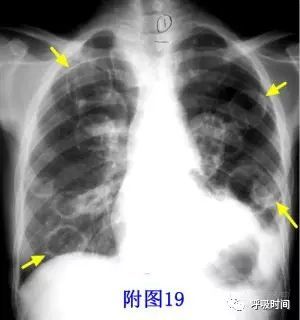

图 19 肺转移瘤:双肺弥漫分布多个圆形薄壁空洞